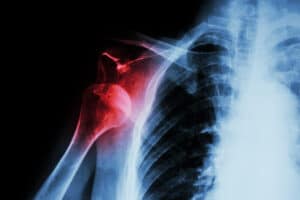

Shoulder Instability and Chronic Dislocation

The shoulder is a special joint as it is really a combination of several joints—combined in such a way by an intricate arrangement of muscles and tendons—that provides the arm a wide range of motion, flexibility and stability. The rotator cuff is a group of four shoulder muscles that surround the top of the upper … Continue reading Shoulder Instability and Chronic Dislocation